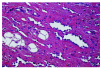

Ambos casos revelaron hallazgos microscópicos totalmente superponibles, consistentes en una proliferación irregular de canales vasculares dispuesta en un patrón infiltrativo que disecaba el tejido conectivo de la dermis profunda e invadía los lobulillos adiposos de la hipodermis (fig. 2). Los vasos, de paredes finas, presentaban una disposición rectilínea y a veces se advertían bifurcaciones que daban lugar a formaciones pseudopapilares intraluminales. Las células que tapizaban los vasos se disponían en monocapas de células monomorfas con núcleos prominentes a modo de tachuelas (fig. 3). Las luces vasculares aparecían vacías, sin hematíes y ocasionalmente contenían abundantes linfocitos. La atipia citológica era escasa y no se observaban estratificación ni figuras de mitosis. En el estroma existían ocasionales focos de linfocitos maduros (fig. 4). Con las técnicas inmunohistoquímicas, en el caso 1 se observó positividad difusa en las células endoteliales de los canales vasculares proliferados para CD31 y de manera focal para el factor VIII. La reacción para el CD34 fue débil e irregular. El índice de proliferación con el anticuerpo Ki-67 fue menor del 1%. En el caso 2 existía mayor tendencia a la formación de papilas y menor infiltrado linfocitario, y la inmunotinción de las células tumorales era más evidente con el CD34 (fig. 5) que con el CD31 y el factor VIII.

Fig. 3.--Caso 2: canales vasculares tapizados por monocapas de células monomorfas con núcleos prominentes a modo de tachuelas (H&E, 400x).

Fig. 4.--Caso 1: agregados linfoides estromales y endoluminales (H&E, 200x).